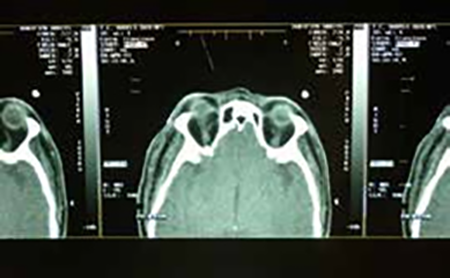

F.F.M. Masculino de 72 años de edad. A diferencia del caso precedente el paciente concurre a la consulta por motivos refractivos, y en el interrogatorio sobre antecedentes oftalmológicos relata que 15 años antes perdió la visión de su OD a raíz de un intento de robo por parte de dos masculinos los que lo sorprenden subiendo a su rodado obligándolo a marcharse con ellos con el mismo. Ante su ansiedad y al querer resistirse uno de los malvivientes le efectúa un disparo a unos 50 cm. de distancia el que ingresa por piel de párpado inferior OD ángulo ínfero-interno, y luego de un curioso recorrido intracorporal termina alojándose en la axila izquierda, en una trayectoria que Bonnet describe como proyectiles migradores 2 lesionando en su camino órbita y globo ocular derecho y parcialmente el plexo braquial izquierdo. A consecuencia de los mismos el paciente tiene ausencia de visión OD, anestesia en el territorio inervado por la segunda rama del trigémino derecho, e impotencia funcional para elevar el miembro superior izquierdo. El paciente refiere que hubo desprendimiento retinal que fue operado poco tiempo después del incidente. Cinco años después se lo operó por catarata traumática.

• Fondo de ojo: OD extensa área de denudación coriorretinal, atrofia óptica, gran movilización de pigmento.

• OI sin particularidades (Figuras 5 y 6)

Figura 6: radiografía de craneo, tomografía computada, radiografía de tórax frente y perfil.